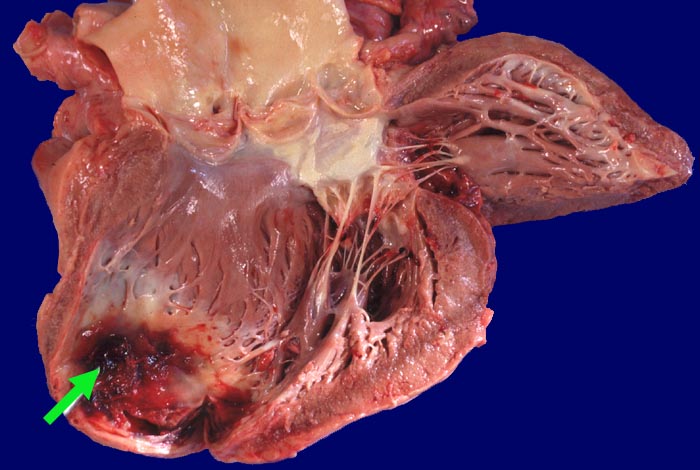

Herzwandaneurysma mit Thrombose

Wandverdünndung und Ausbuchtung im Bereich einer Myokardinfarktnarbe der Herzspitze. Dem Aneurysma ist wenig thrombotisches Material aufgelagert.

Cor bovinum (700g). Alter diskontinuierlicher Myokardinfarkt der rechten Herzkammer. Subakuter Myokardinfarkt der Hinterwand. Morbus embolicus.